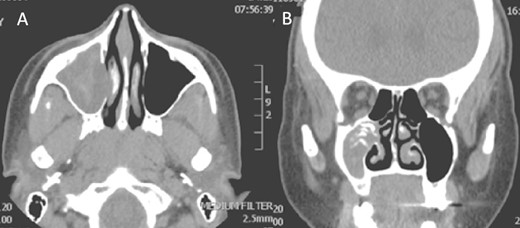

A 30-year-old lady presented to the clinic with a complaint of right facial pain, recurrent rhinorrhea with post-nasal discharge, nasal endoscopic examination was unremarkable. A non-contrast computed-tomography scan (NCCT) of the paranasal sinuses (Fig. 1) was suggestive of isolated right fungal maxillary fungal ball (FB). The patient underwent endoscopic sinus surgery (ESS) with (Fig. 2) right middle meatal antrostomy and removal of fungal debris. The patient was followed up regularly and remained symptom free.

Axial (A) and coronal (B) images of a nonenhanced CT scan of the paranasal sinuses showing right maxillary sinus complete heterogenous opacification.